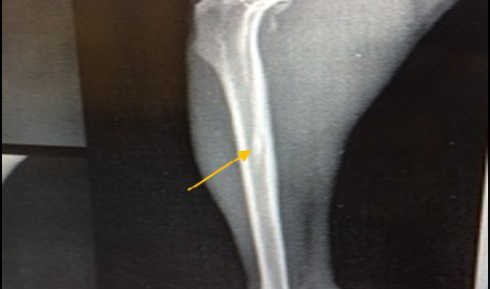

Site of operation, shows mediolateral view of the right tibia in non-infected group 21 days post-operatively, the hole had disappeared completely (healed, ML view)